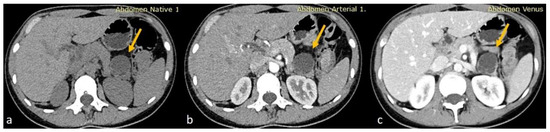

An MRI performed one year after the initial imaging and two months before admission revealed an increase in the size of the pancreatic cystic lesion to 4.5 cm (Figure 3 and Figure 4) with enhancement of its thin wall and internal septa, confirming its progressive nature. The lesion continued to compress the pancreatic tail and the greater curvature of the stomach, without causing pancreatic duct dilation. The imaging also showed low signal intensity on T1- and high signal intensity on T2-weighted sequences, with capsule enhancement post-contrast, suggesting a mucinous cystic neoplasm (Figure 4). Additionally, the MRI confirmed the presence of a 9 mm hemangioma and a small liver cyst, both unchanged from prior scans. No enlarged retroperitoneal lymph nodes were observed, and the MRCP findings showed normal intrahepatic bile ducts, common hepatic bile duct, gallbladder, and pancreatic duct. No abnormalities were found in the spleen, kidneys, or adrenal glands.

Figure 3.

(a,b) Axial sequences of the upper abdomen comparison showed an increase in the lesion size.